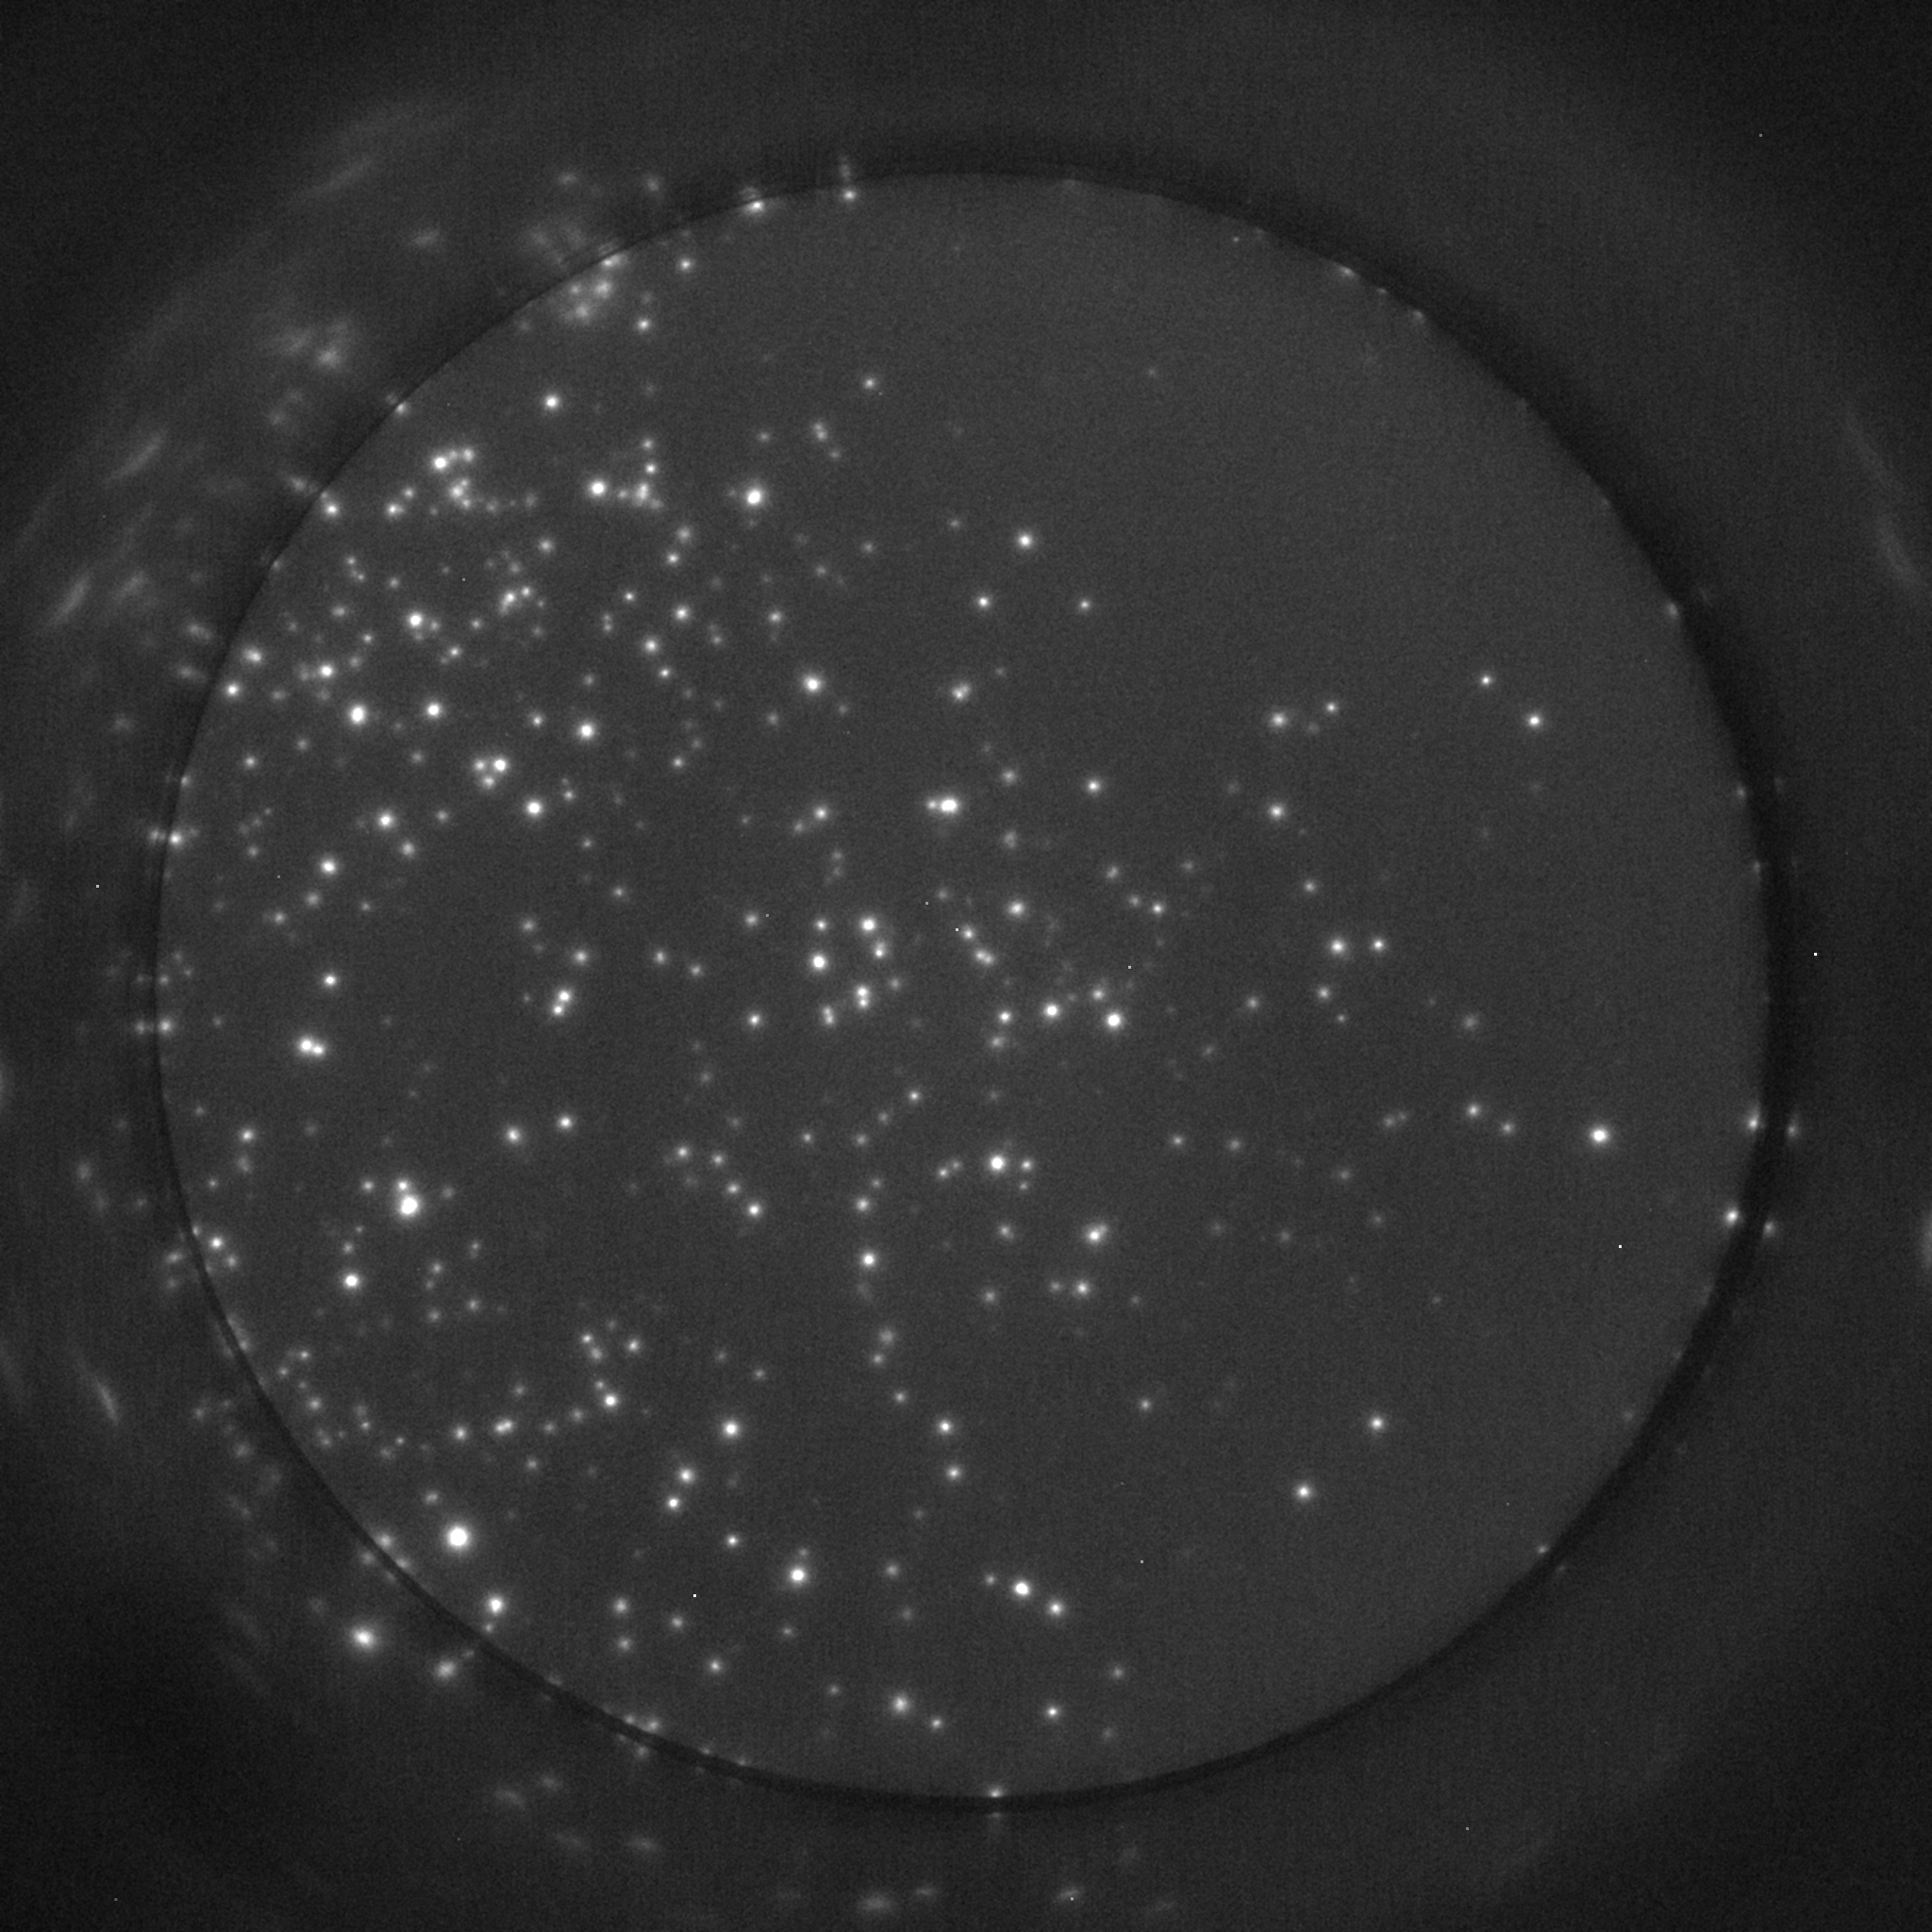

We analyzed a real Fluorospot image for which human expert labeling was available. This image was obtained by using FITC dye as a marker for some relevant analyte, and was captured by an RGB sensor that yielded a raw image with a dynamic range of . The data was subject to a Bayer filter, i.e., neighboring pixels exhibited different sensitivities to light intensity at the FITC wavelength (). To compensate this difference, we weighted each pixel correspondingly to estimate the luminosity, and used to weight the prediction error at each pixel according to its sensitivity. Furthermore, we selected the area that comprised the well manually, and fixed for all points outside it.

We used the algorithm in Fig. 2 with , , and the sequence proposed in [16]. The underlying parameters (see [7]) were set to . We run the algorithm for 10000 iterations, which were more than those needed for convergence. The resulting F1-Score was with precision and recall . On the left panel of Figure 3, we show a grayscale representation of the image under study, while on the right panel, we show both the detections proposed by the human expert (orange squares) and the ones proposed by our algorithm (yellow circles), on a specific section of the image.

In our opinion, both sets of detections are of comparable quality, with our algorithm being more precise in terms of cell locations and the human labeler obtaining higher recall for isolated cells. However, one has to take into account that the detections obtained by our algorithm have been thresholded to match the criteria of this specific expert, and thus, the absence of weaker spots in the set of detections can be explained by inconsistent inclusion criteria in the human labeling. A final relevant difference between the two sets of detections is that our algorithm uses the observation model to evaluate the whole shape of spots in terms of possible cells, instead of mainly relying on local luminosity. Hence, the algorithm includes detections that are weaker but fit the shape of cell-generated spots, as the apparent false positive in the middle-right region of the image. This also results in the correct decomposition of clusters of cells, as it is clearly the case of the large spot in the upper-right region of the image.